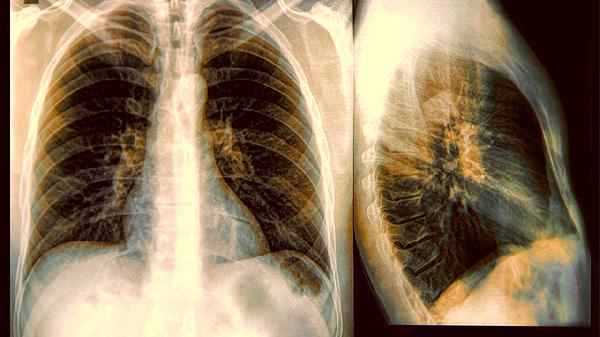

风寒型急性支气管炎初期出现阵发性干咳伴胸骨后疼痛时,可在医生评估后使用。该药能缓解气管黏膜充血水肿,但若出现脓痰、发热等细菌感染征象,需联用阿莫西林胶囊等抗生素治疗。

慢性支气管炎遇寒冷刺激急性发作时,对于咳嗽痰多色白者有一定缓解作用。但该药不宜长期使用,合并肺气肿或哮喘者需搭配氨茶碱片等支气管扩张剂,避免单纯依赖止咳药物延误治疗。